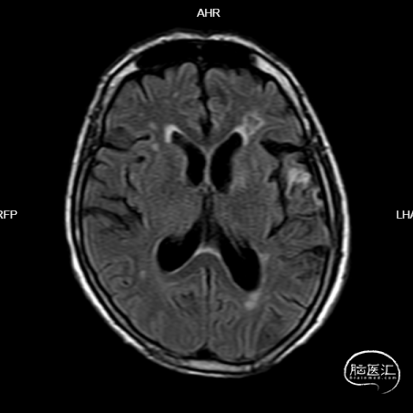

头颅MRI:未见明显新鲜梗死灶。